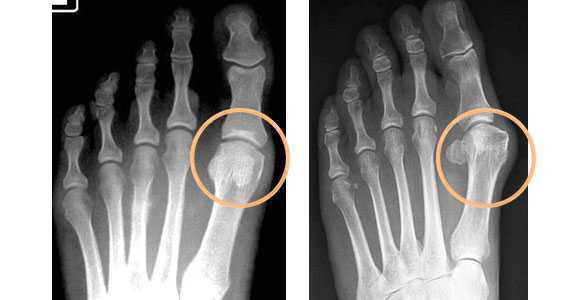

- Рентгенография стопы. Является основным диагностическим методом при Hallux valgus. Рентгенолог производит специальные измерения, на основании которых определяет степень патологии. Наряду со степенью деформации при изучении рентгеновских снимков оценивают выраженность артрозных изменений. О наличии артроза свидетельствует сужение суставной щели, деформация суставной площадки, краевые разрастания и остеосклероз субхондральной зоны.

Рентгенография стопы. Вальгусная девиация первого пальца стопы, с увеличением угла отклонения 1-го пальца и угла между осями 1-й и 2-й плюсневых костей.